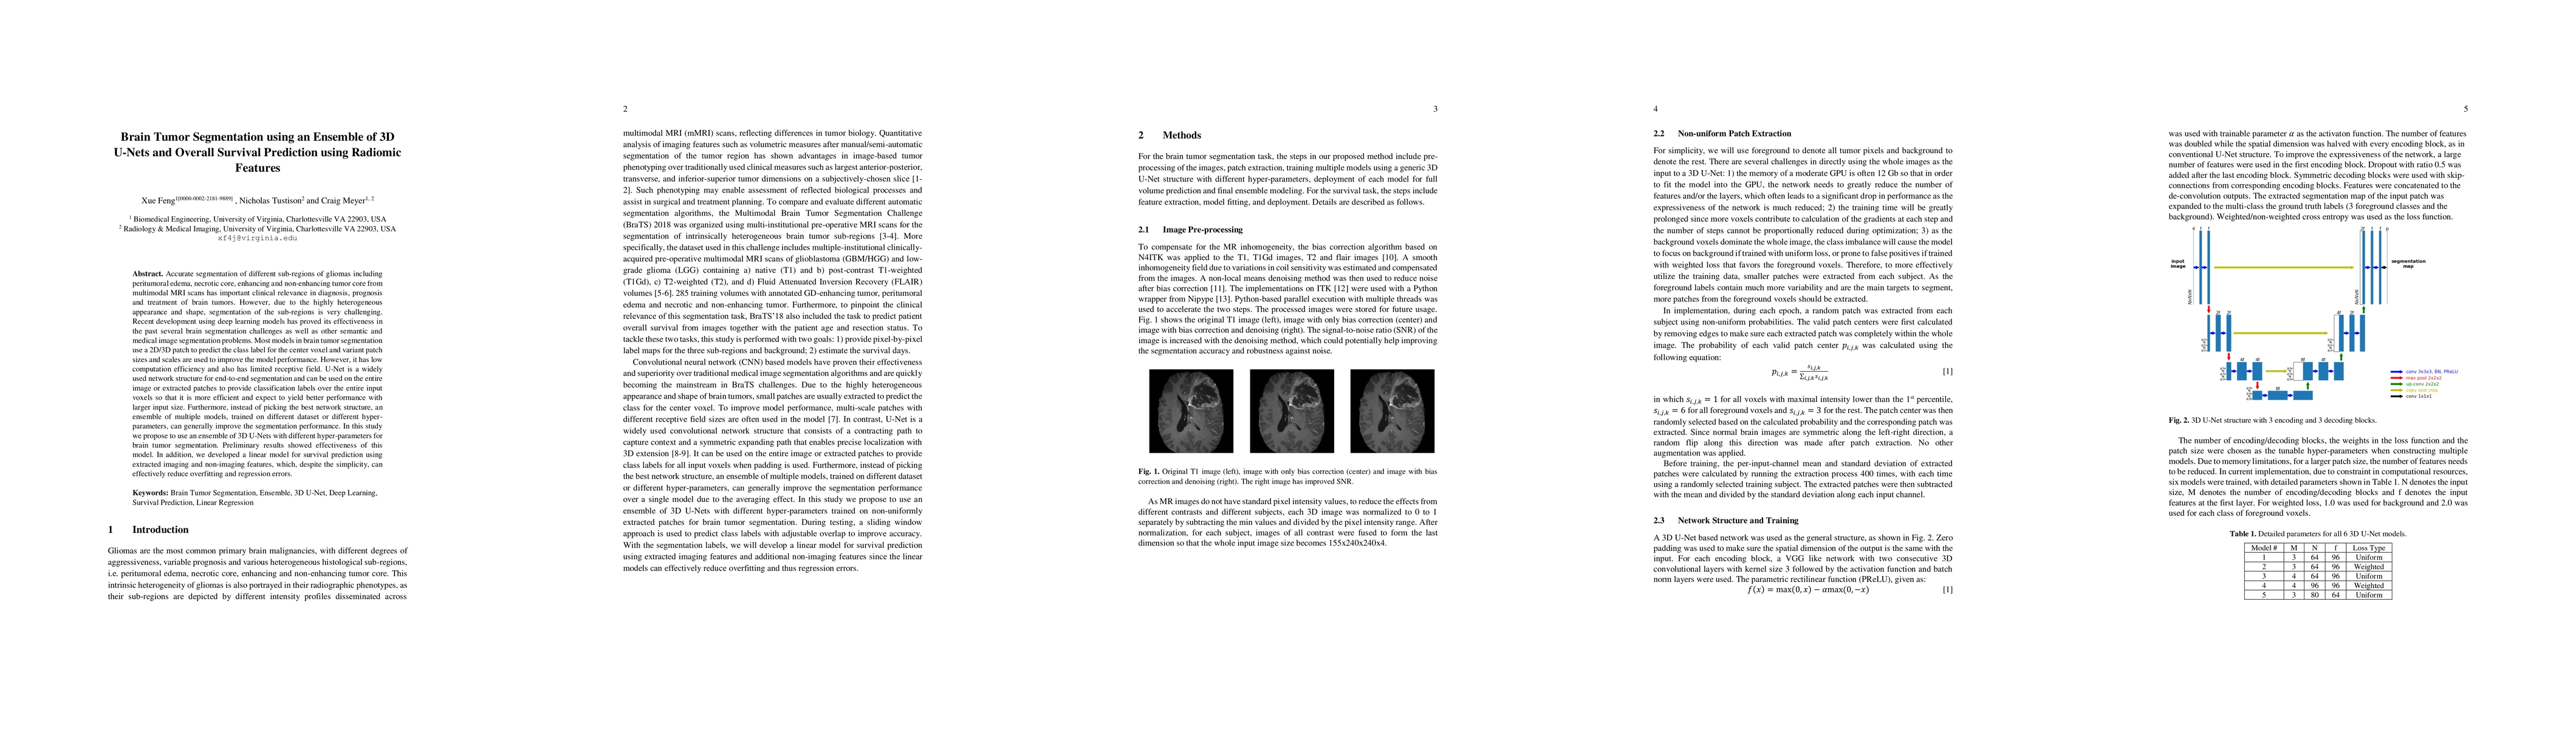

Accurate segmentation of different sub-regions of gliomas including peritumoral edema, necrotic core, enhancing and non-enhancing tumor core from multimodal MRI scans has important clinical relevance in diagnosis, prognosis and treatment of brain tumors. However, due to the highly heterogeneous appearance and shape, segmentation of the sub-regions is very challenging. Recent development using deep learning models has proved its effectiveness in the past several brain segmentation challenges as well as other semantic and medical image segmentation problems. Most models in brain tumor segmentation use a 2D/3D patch to predict the class label for the center voxel and variant patch sizes and scales are used to improve the model performance. However, it has low computation efficiency and also has limited receptive field. U-Net is a widely used network structure for end-to-end segmentation and can be used on the entire image or extracted patches to provide classification labels over the entire input voxels so that it is more efficient and expect to yield better performance with larger input size. Furthermore, instead of picking the best network structure, an ensemble of multiple models, trained on different dataset or different hyper-parameters, can generally improve the segmentation performance. In this study we propose to use an ensemble of 3D U-Nets with different hyper-parameters for brain tumor segmentation. Preliminary results showed effectiveness of this model. In addition, we developed a linear model for survival prediction using extracted imaging and non-imaging features, which, despite the simplicity, can effectively reduce overfitting and regression errors.